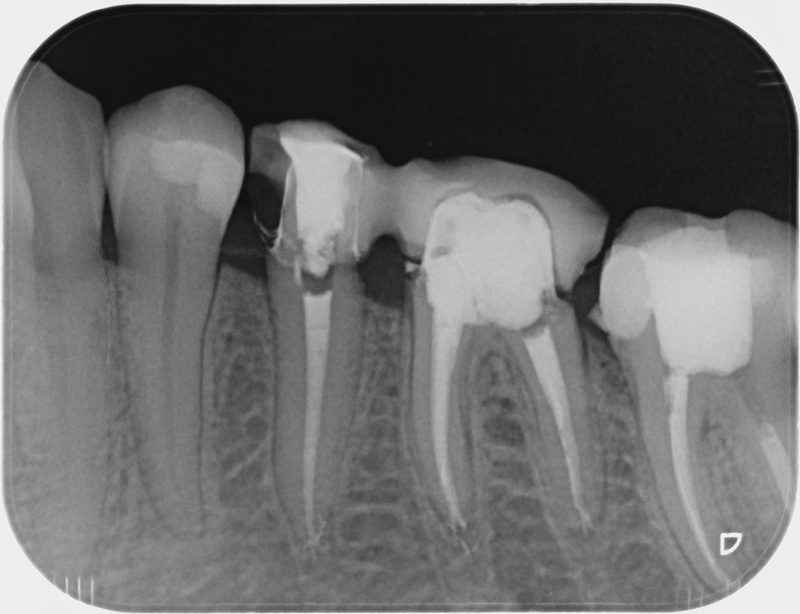

• Reprise de traitement endodontique : La manœuvre consiste à retourner à l’intérieur des racines d’une dent déjà traitée. Il arrive occasionnellement qu’une nouvelle inflammation se déclare suite à une reprise de carie ou une fracture de la dent, ou si le premier traitement endodontique est incomplet. Après s’être assuré que la dent lésée était conservable, il convient de désinfecter de nouveau le réseau canalaire parfois très complexe. La nouvelle obturation des canaux devra être protégée aussi rapidement que possible pour éviter une éventuelle contamination bactérienne.

Avant

Après